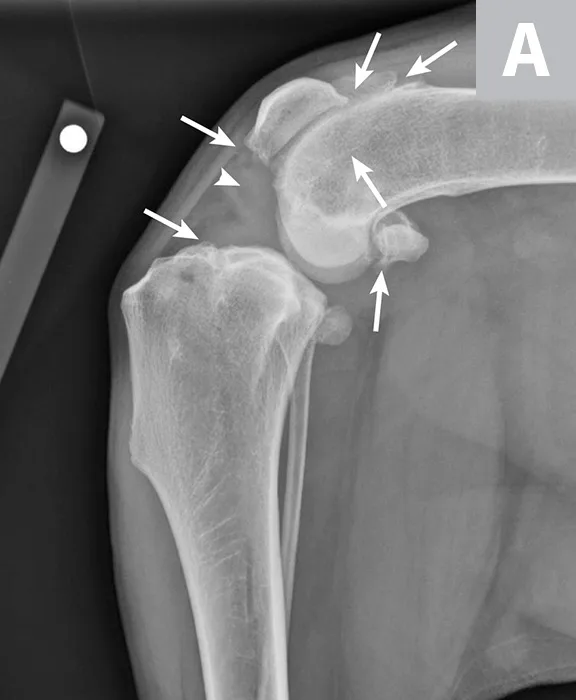

FIGURE 2

Mediolateral (A) and craniocaudal (B) radiograph projections of a 3-year-old spayed mastiff with right CCL rupture and medial meniscal tear. Osteophytes are present on the femoral condyles, patella, fabellae, and tibial plateau (arrows). There is increased soft tissue opacity in the joint space consistent with joint effusion (arrowhead). In addition, there is cranial displacement of the tibia relative to the femur on the lateral projection. These signs combined are consistent with CCL rupture.

Clinical history and orthopedic examination are key to diagnosing meniscal injury, but diagnosis cannot be confirmed using only these methods. Orthogonal radiography of the affected stifle joint can be used to evaluate the presence and severity of osteoarthritis and can help rule out other pathologies (eg, osteochondritis dissecans, fracture, neoplasia) of the stifle. In dogs with CCL rupture and possible meniscal injury, osteophytosis, increased soft tissue opacity in the joint space (ie, joint effusion), and increased soft tissue opacity on the medial aspect of the joint (ie, medial buttress) are commonly seen on radiographs (Figure 2); however, it is possible to see little to no osteoarthritis in acute injuries. The meniscus cannot be directly visualized on radiographs and identification of meniscal tears is limited, even with computed tomography arthrography.32,33 A skilled ultrasonographer may be able to identify some tears in the meniscus34-37; however, MRI is a more readily available and reliable, noninvasive method to evaluate the presence of meniscal tears.37-40